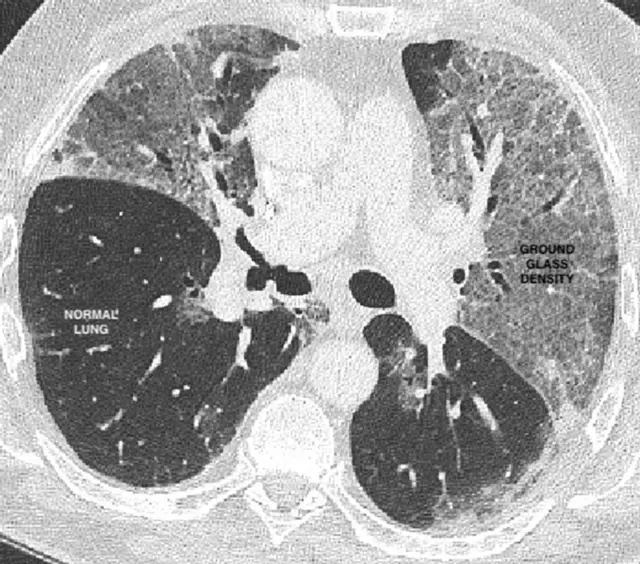

건강한 폐는 대부분 공기로 가득 차 있기 때문에 CT 촬영에서 검은색으로 나온다. 그러나 코로나19에 걸린 경우 화장실의 불투명한 유리창과 비슷한 '유리 가루' 형태를 보인다.

사진 출처, UCL

여기에는 한 가지 분명한 문제가 있다. 다른 호흡기 질환도 이런 형태를 일으킬 수 있다. 때문에 폐 손상이 코로나19 때문인지, 겨울 독감 때문인지를 분별하기 어려울 수도 있다.

제이컵스 전문의는 내게 이렇게 말했다. "환자의 혈액이나 조직 검체를 가지고 있지 않기 때문에 코로나19인지 아닌지를 확정할 수는 없을 겁니다. 하지만 1월에서 3월로 갈수록 겨울 독감의 발생은 줄어들게 돼 있죠."